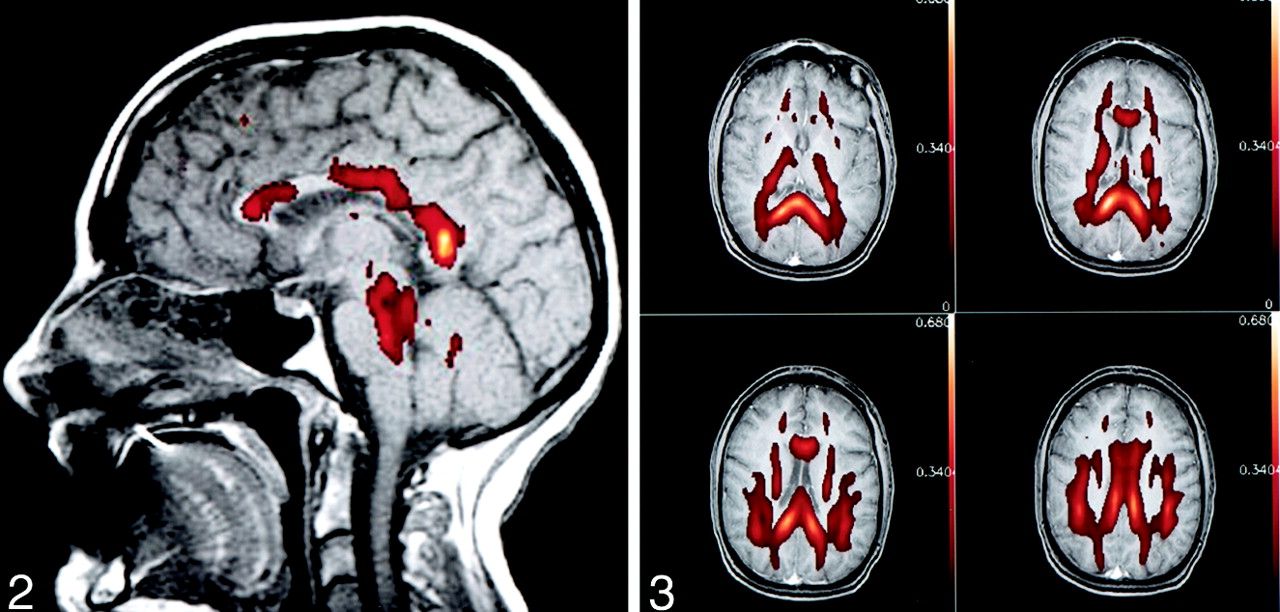

Figures 2 and 3 demonstrate typical findings. Figure 2 is a color representation of an anisotropy index map overlaid on a midsagittal spin-echo T1-weighted image through the corpus callosum in a single patient. Figure 3 shows the same anisotropy map data in the axial plane, overlaid on spin-echo T1-weighted images through the corpus callosum (also in a single patient). Both figures show that anisotropy values in the posterior portions of the corpus callosum were greater than those in the anterior portions.

Typical appearance of anisotropy in healthy human adult brain. Anisotropy maps obtained with the volume-ratio method are represented by color overlay on a gray-scale sagittal spin-echo T1-weighted image. Note the increased anisotropy of the posterior aspect of the corpus callosum compared with that of the anterior portion.

Typical appearance of anisotropy in healthy human adult brain. The same anisotropy maps from Figure 2 were overlaid on four axial spin-echo T1-weighted images through the corpus callosum.